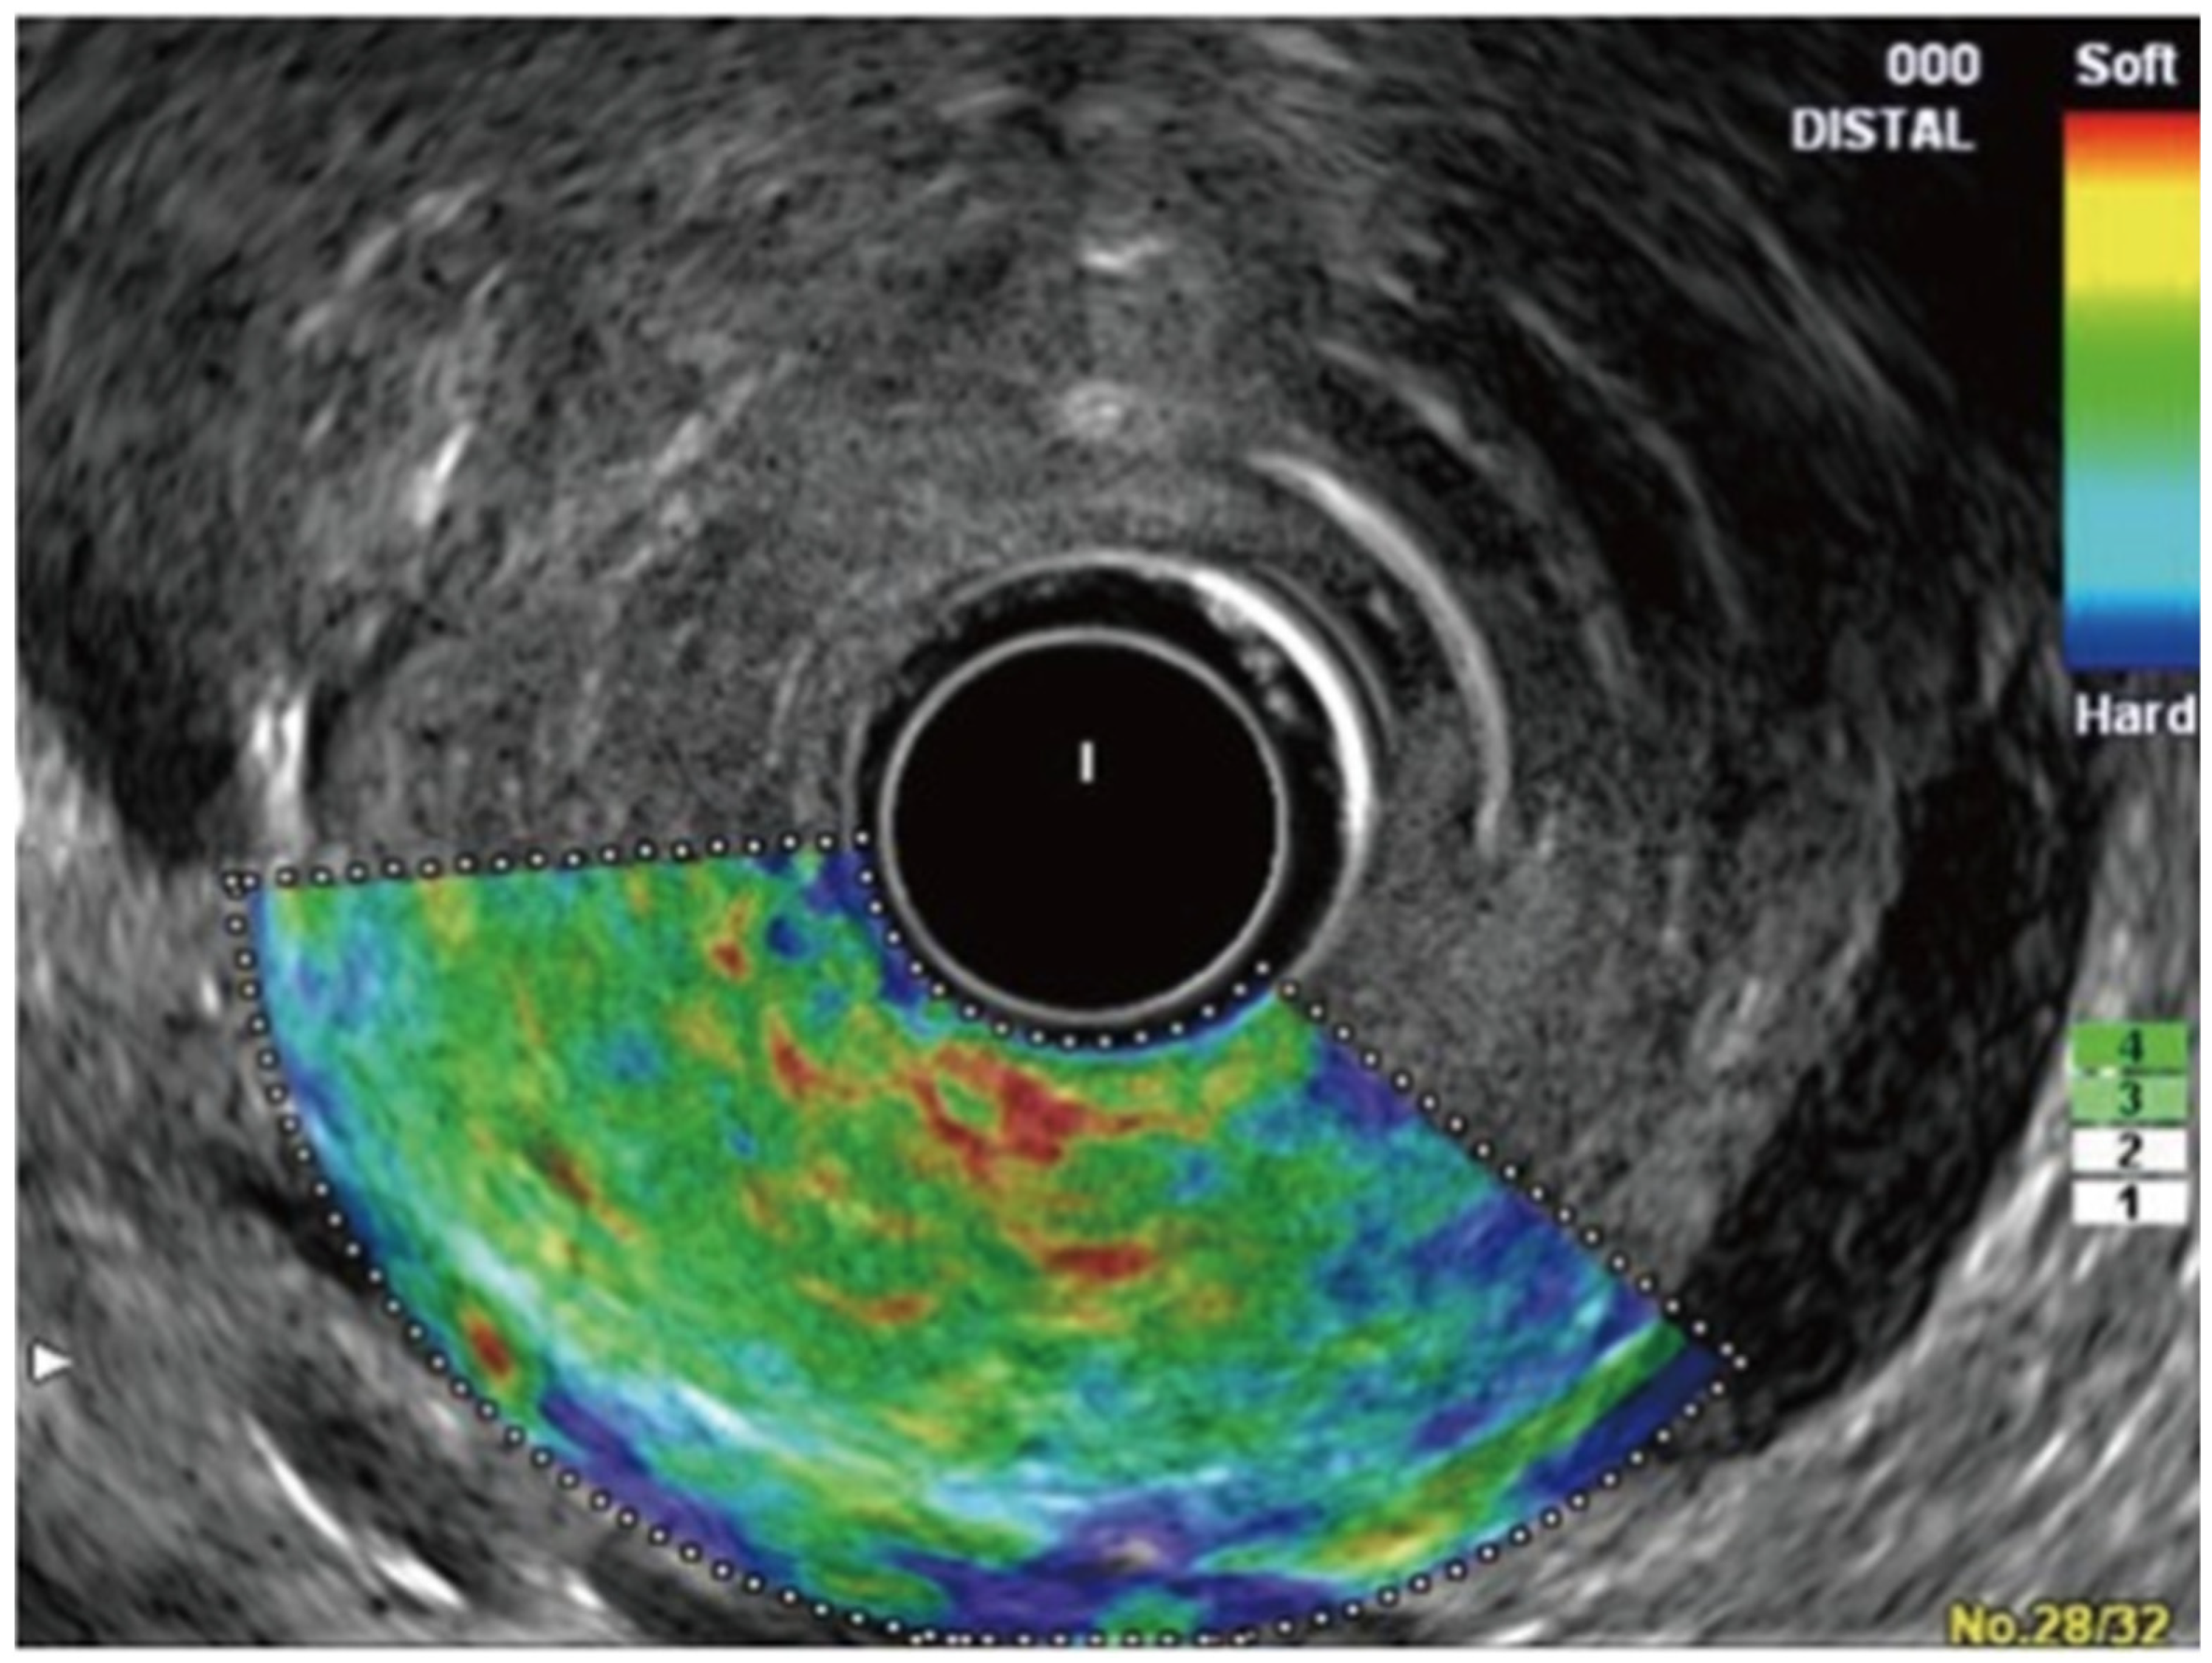

- Strain Elastography (Qualitative Elastography): It estimates the stiffness of the tissue by measuring the degree of strain [29,52]. The results are interpreted with the help of a colored scale, wherein red-green areas indicate softer tissues and blue areas indicate stiffer tissues [29,52]. The main limitations of qualitative elastography are that it lacks reproducibility as the interpretation of the colors is highly operator-dependent, and it provides limited information when comparing results for different patients and lesions [54,55].

- Shear-Wave Elastography (Quantitative Elastography): It measures tissue stiffness by measuring the propagation of the shear waves, which is the emission of focused waves from the probe to the target lesion, also known as acoustic radiation force impulse [29]. Another method of shear-wave elastography is the semi-quantitative analysis, which allows for the measurement of tissue stiffness by calculating the strain ratio (ratio of stiffness of area of interest on the target tissue and smaller region of interest of a reference tissue) and strain histogram technique where an average hue histogram represents the colors and thereby the stiffness of the tissue [56]. It is important to note that only strain elastography is available with EUS for the evaluation and characterization of pancreatic lesions [29].